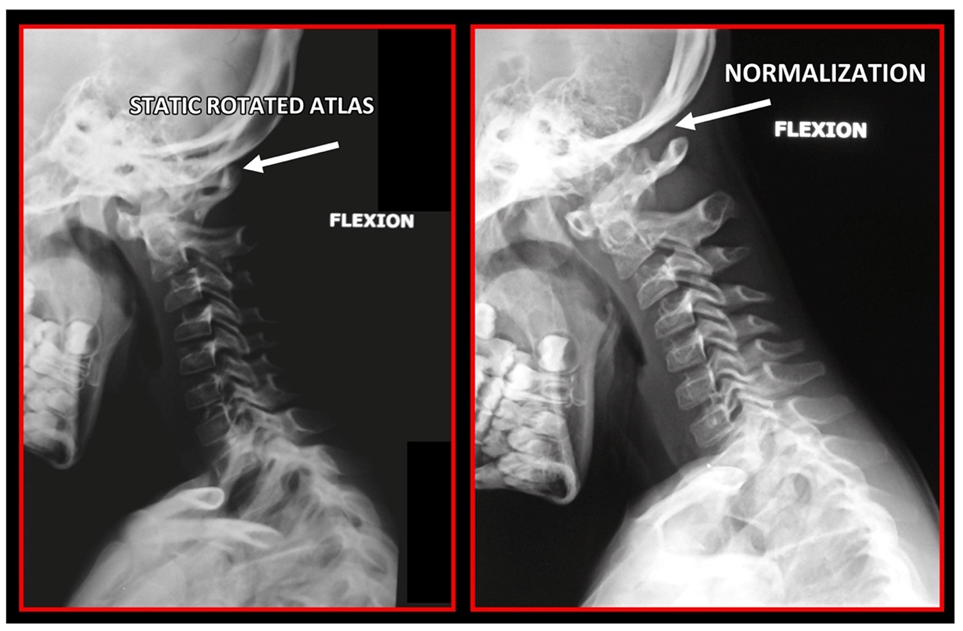

11.5. Axis and Atlas Derotation